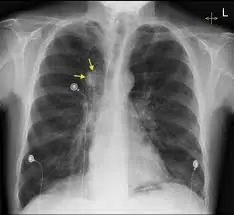

4 สัญญาณเตือนปัญหาหลอดเ.ลื.อดส.มอง ที่ไม่ควรมองข้าม

4 สัญญาณเตือนหลอดเลือดสมอง ที่คุณไม่ควรมองข้ามเด็ดขาด